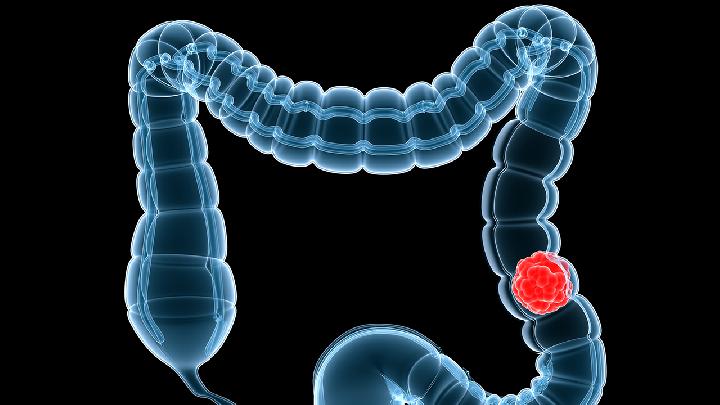

做妇科手术哪里好